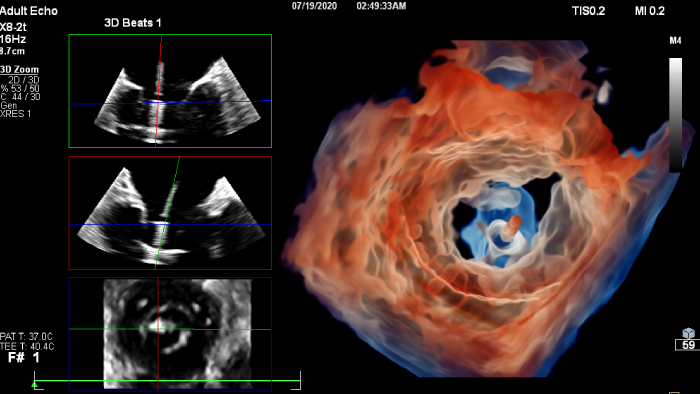

If you were registered for ESC 2023, but were not able to attend the satellite symposium, you can still view it through the ESC website. Top cardiology thought leaders addressed some of the major challenges in peri-interventional and diagnostic echocardiography, such as advancing and complementing imaging techniques during tricuspid valve interventions, a revolutionary imaging workflow for occlusion of the left atrial appendage, and the importance of first-time-right ultrasound imaging during cancer therapy.

You can still access recordings of 4 full days of hands-on workshops about best practices in multimodality cardiac imaging with expert teams. See first-time-right imaging for cardiac care, including valvular and related diseases, cardiomyopathies, and intracardiac masses and cardiac tumors. Sign up to receive access to these on demand sessions and other news about Philips and cardiac care.

Increase diagnosis confidence and clinical efficiency through superior image quality, advanced quantification tool and automation technology.